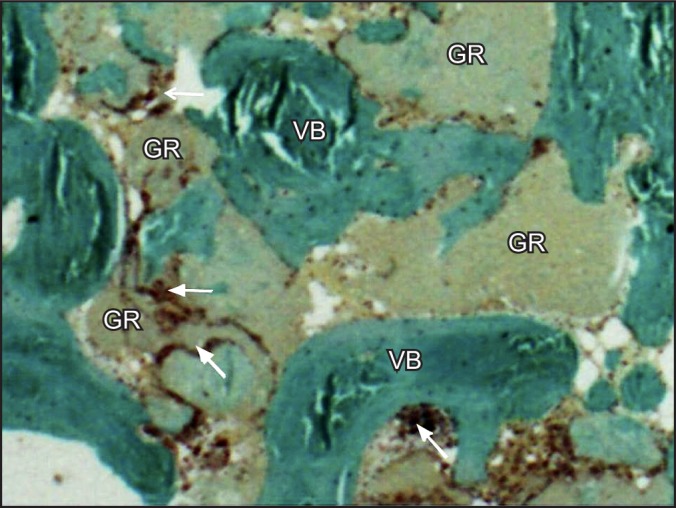

Material and methods: Thirty patients, with single extraction sockets without severe bone wall defects in the premolar/molar region, were included. Ten extraction sockets were grafted with porcine-derived bone and covered with collagen membrane (group 1), 10 sites were covered with collagen membrane alone (group 2), and 10 sites healed spontaneously (group 3). After 4 months of healing, 26 (8 in group 1, 9 in group 2, and 9 in group 3) bone core specimens were harvested for histologic evaluation, then dental implants were placed.

Results: Sites in the group 1 and in the group 2 showed similar histologic and histomorphometric results without significantly differences in the percentage of vital bone (57.43% [SD 4.8] vs. 60.01% [SD 3.2]), and non-mineralized connective tissue 22.99% (SD 5.3) vs. 18.53% (SD 6.2). In group 1 a 16.57% (SD 3.8) of residual material was found.